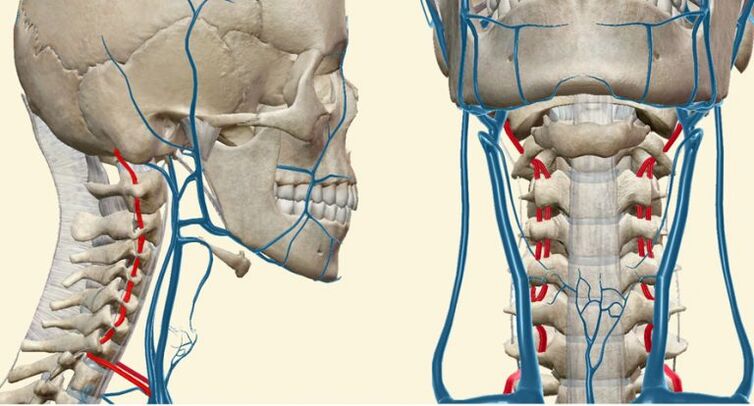

Asinsvadu sindroms

Šis sindroms ir saistīts ar asins piegādes trūkumu (išēmiju) ar barošanas artērijas pakāpenisku slēgšanu (oklūziju).

Šim sindromam ir īpaša nozīme dzemdes kakla osteohondrozē, jo šajā apgabalā notiek lielas mugurkaula artērijas saspiešana. Šī parādība izskaidro neiroloģiskos simptomus smadzeņu hipoksijas dēļ.

85% cilvēku asins piegāde muguras smadzeņu krūšu, jostas daļas un sakrālās daļās notiek caur Adamkiewicz artēriju. Asins cirkulācijas izmaiņas caur šo trauku noved pie skābekļa bada un periodiska klaudikācijas sindroma attīstības. To raksturo vājuma un nejutīguma sajūta kājās, kas parādās ar muskuļu spriedzi.